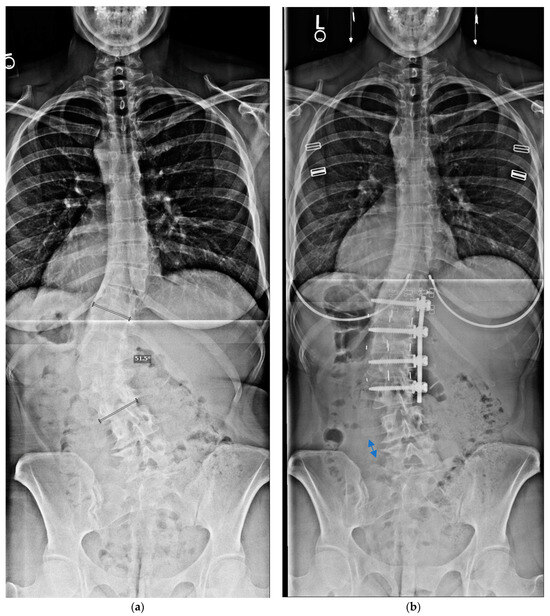

Maximizing the number of caudal levels not fused is thought to be advantageous, not only in terms of sparing mobility, but also in minimizing adjacent segment disc degeneration below the fusion construct [11,12]. Prior reports have suggested that anterior and/or lateral fusions can reduce the number of motion segments treated relative to PSF. Additionally, realigning the spine favourably improves the biomechanical loading of the adjacent lower discs [28]. The present study supports that contention. Most of our patients had their fusion at L2 or L3 as the lowest instrumented vertebral, LIV, level. Our few patients with a lower LIV or greater residual lumbosacral, LS, curvature had distal degeneration, with two having additional surgery. Interestingly, two of the adult AIS patients had a resolution of significant leg pain; one had foraminal stenosis and the other a posterolateral disc herniation extending into the foramina, both at the level below the fusion construct and on the concavity of the LS fractional curve. Upon correction of the spinal deformity, which secondarily corrected the LS curve, the disc spaces and angulation were neutralized (Figure 4a,b), and radiographs suggested that the foramina opened on the concavity of the fractional curve below the primary curve, which presumably resulted in their resolution of preoperative leg symptoms.

Figure 4.

Preoperative and postoperative coronal radiographs (a,b) of a patient who had a resolution of left L5 pain symptoms after surgery. This demonstrates increased opening, indicated by the arrows, in the left L4–5 disc height in the fractional lumbosacral curve below the corrected T12–L3 fusion construct.